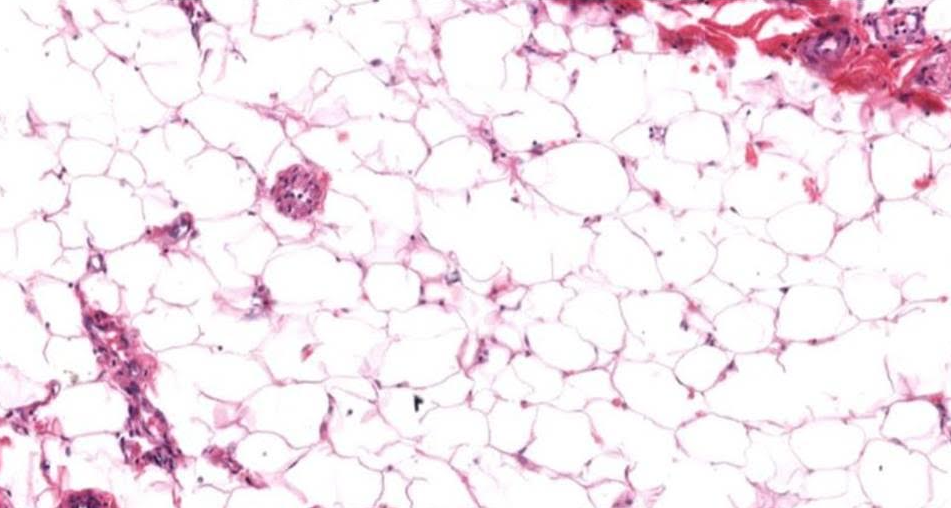

Tecido adiposo unilocular